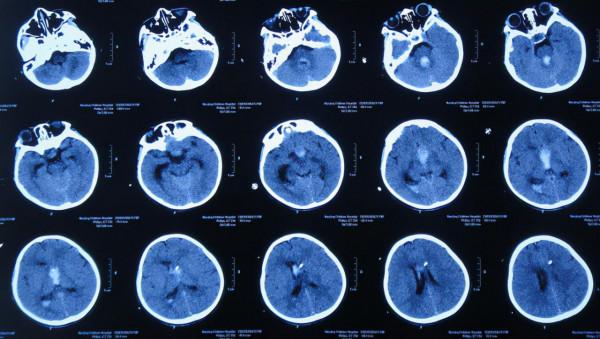

患兒於2019年12月5日下午,出現發熱,家屬自行給予口服布洛芬混懸液治療,但2019年12月6日凌晨2點左右,患兒睡眠中喊頭痛,家屬開車急送至安徽省蕪湖市弋磯山某三甲醫院,去醫院途中病情變重患兒呼之不應;到院後急診查頭部增強CT示蛛網膜下腔出血(圖-1),考慮血管畸形,於凌晨4點急診進行了腦室外引流術;術後當天早晨8點進行了DSA檢查排除血管畸形(圖-2)。

圖-1:2019年12月6日頭部增強CT

腦室外引流術後次日即2019年12月7日,查頭部CT示腦室出血,引流術後狀態(圖-3)。

圖-3:2019年12月7日頭部CT

引流術後3天即2019年12月9日,再次查頭部增強CT掃描示胺區腫瘤(圖-4)。

圖-4:2019年12月9日頭部增強CT